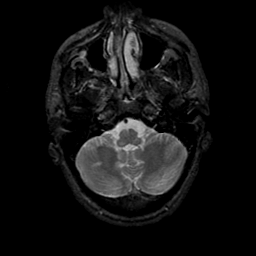

MR Study #9, April 14, 1991 -- Slice #9